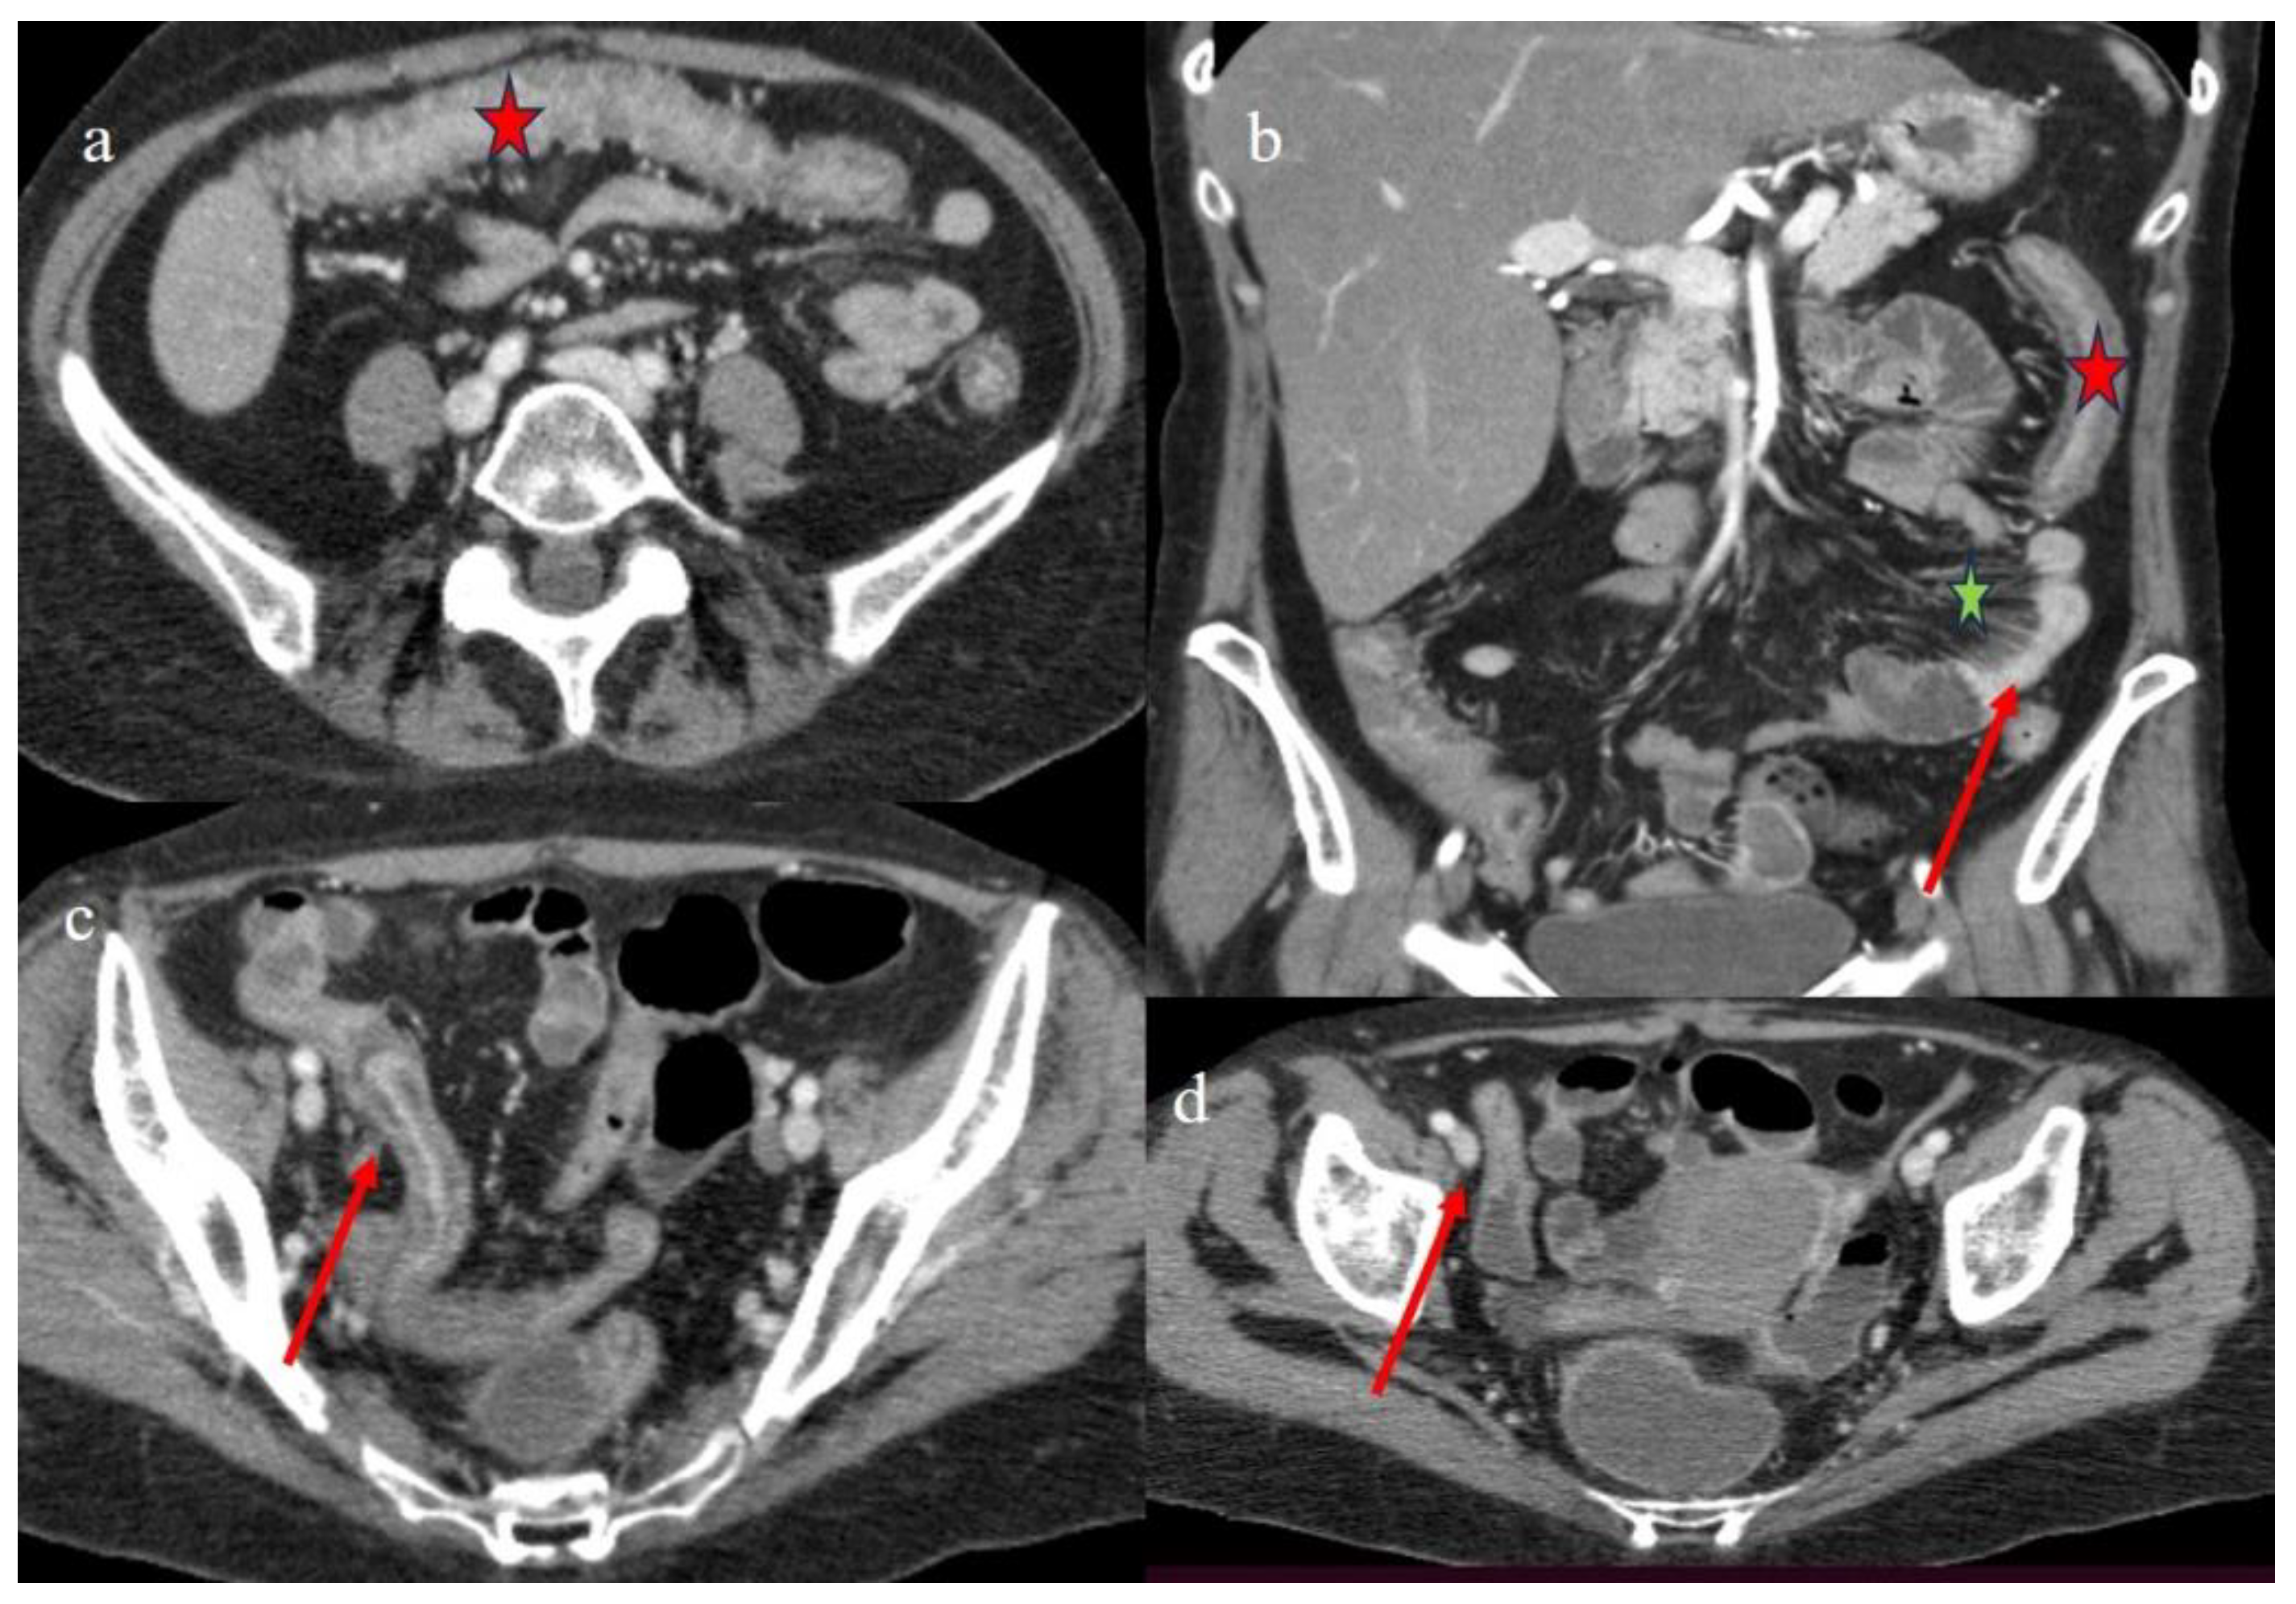

| 3 | P | P | Multisegmental thickness with stratified enhancement at the terminal ileus (on CECT control at 92 days). The CECT control at 129 days showed persistence of mild parietal thickness at terminal ileus and with mucosal enhancement | Diffuse parietal thickness with stratified enhancement (On CECT control at 92 days) The CECT control at 129 days showed colic fluid distension with mild diffuse mucosal enhancement | Diffuse comb sign, mild ascites, and poor reactive mesenteric lymph node | Hepatomegaly and mild gallbladder thickness |